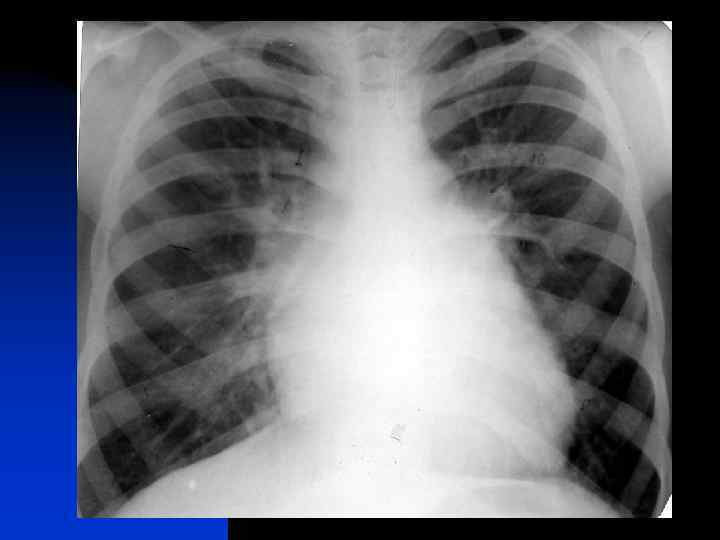

Подозрение на аневризму грудной аорты n Аневризма грудного отдела аорты на рентгенограмме органов грудной клетки

Подозрение на аневризму грудной аорты